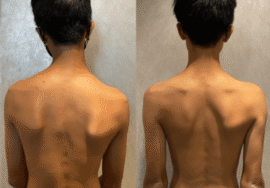

عندما يُشخَّص طفلك أو مراهقك بإصابة في العمود الفقري تُعرف بالجنف أو اعوجاج العمود الفقري، يتساءل الكثير من الأهل فورًا: “هل يحتاج طفلي إلى جراحة؟” هذا القلق طبيعي جدًا، خاصة مع كثرة المعلومات المتضاربة على الإنترنت.

الحقيقة المُطمئنة: في أغلب الحالات يمكن علاج اعوجاج العمود الفقري دون اللجوء للجراحة، خصوصًا عند الاكتشاف المبكر واتباع خطة علاجية صحيحة ومتابعة مستمرة.

إذا لاحظتِ علامات انحناء في ظهر طفلك، أو لاحظتِ عدم تماثل بين الجانبين، فلا تتردد مجانا في استشارة طبيب متخصص.

إذا لاحظتِ علامات انحناء في ظهر طفلك، أو لاحظتِ عدم تماثل بين الجانبين، فلا تتردد مجانا في استشارة طبيب متخصص.

اكتشفوا الانحناء مبكرًا بمراجعة الطبيب والفحص الدوري.